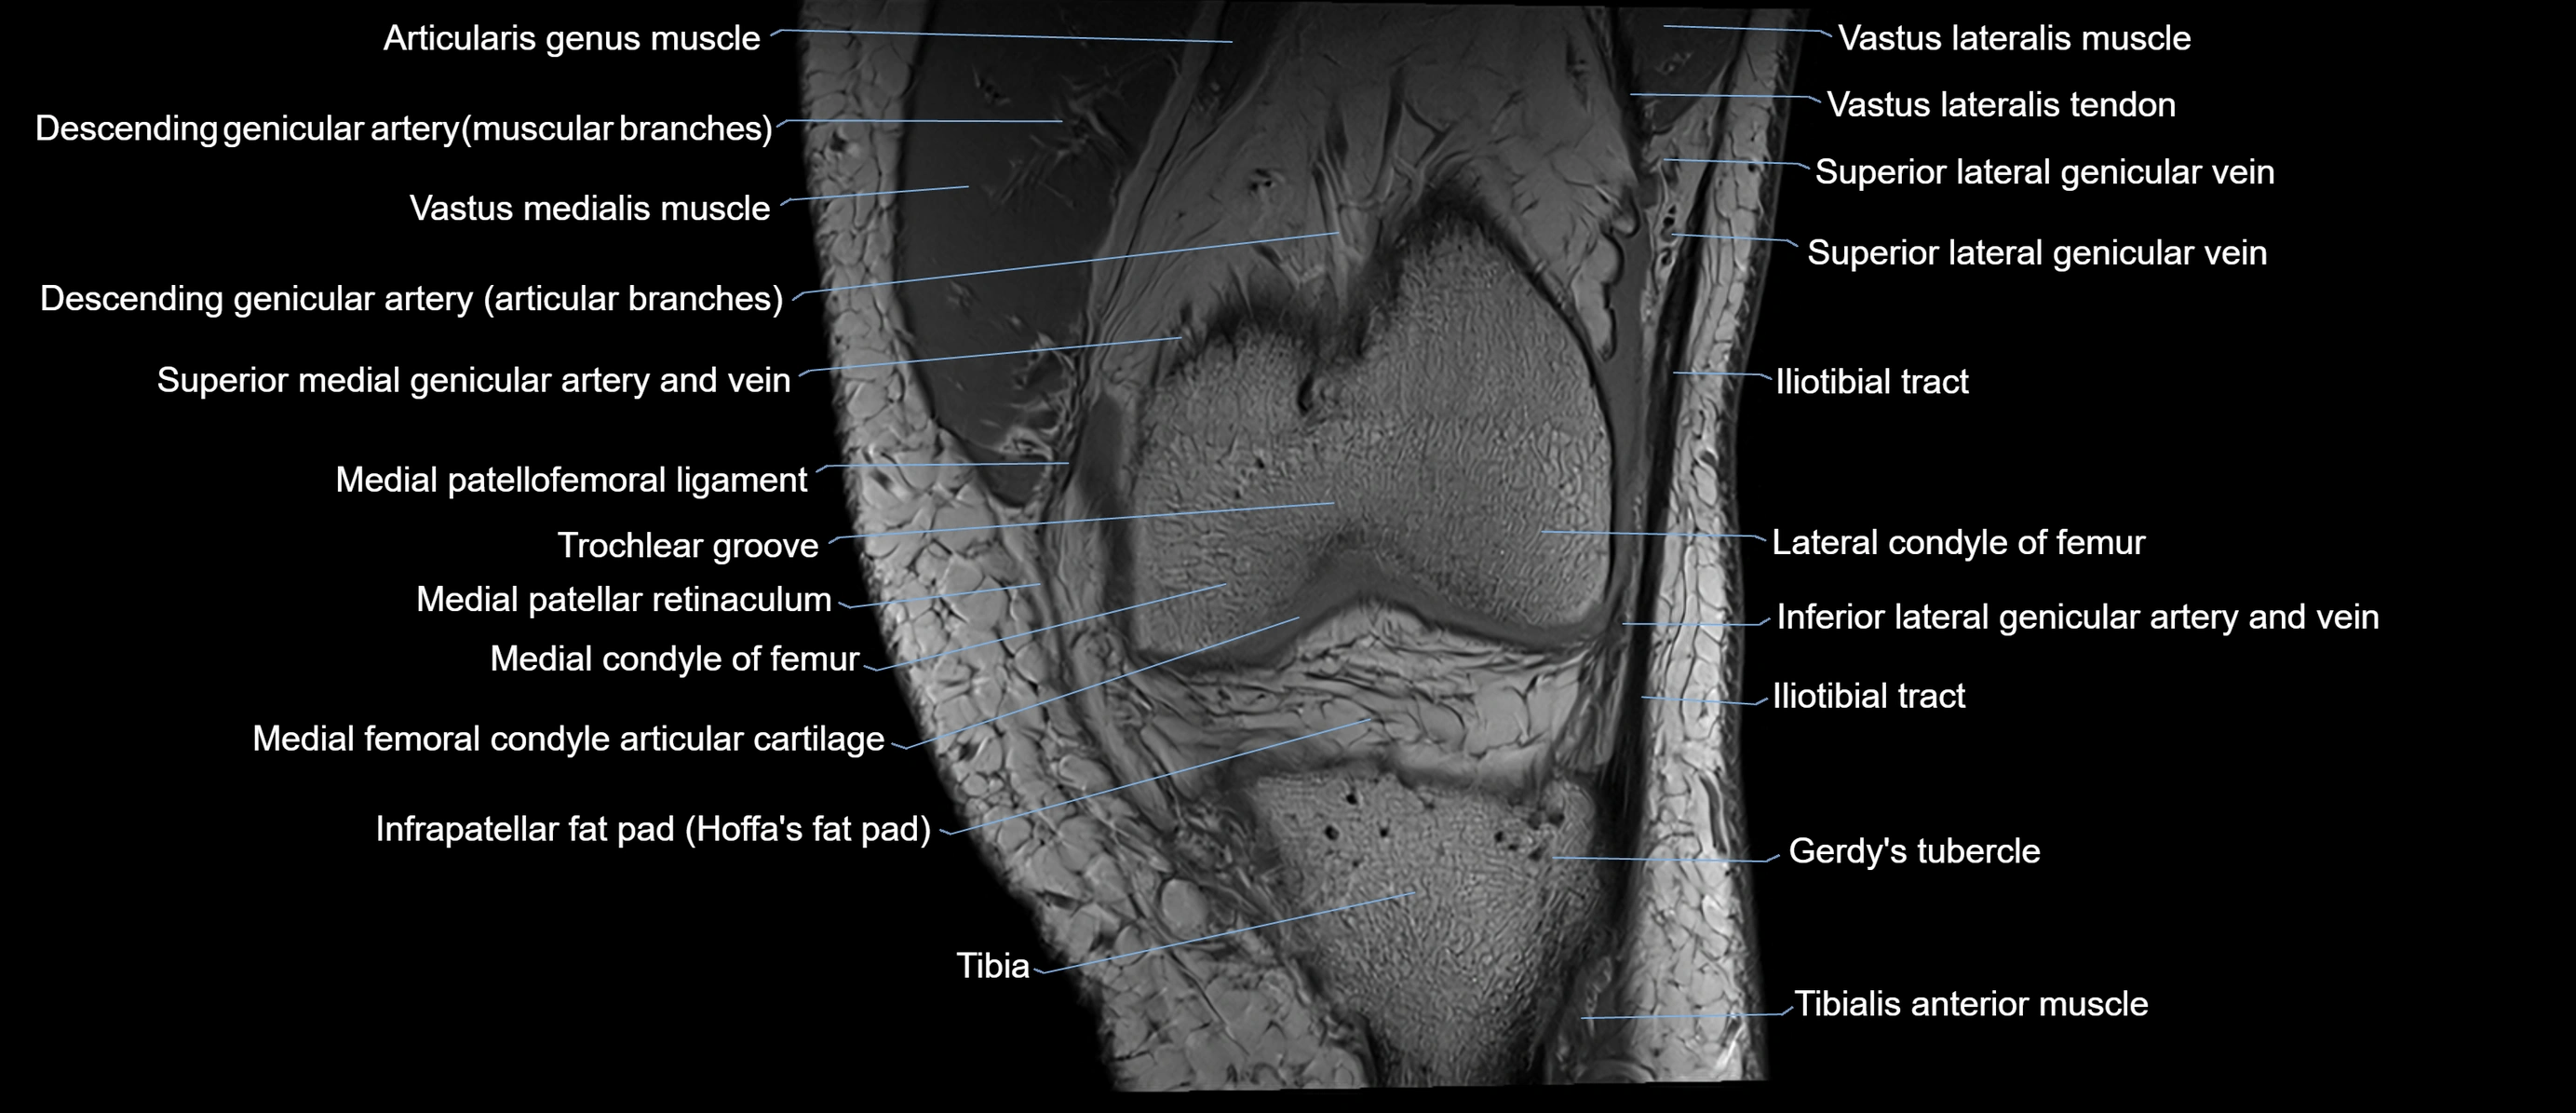

- Descending genicular artery (Articular branches)

- Gerdy’s tubercle

- Infrapatellar fat pad

- Lateral condyle of femur

- Medial condyle of femur

- Medial patellar retinaculum

- Medial patellofemoral ligament

- Superior lateral genicular vein

- Tibia

- Tibialis anterior muscle

- Trochlear groove

- Tubercle of iliotibial tract

- Vastus lateralis muscle

- Vastus medialis muscle